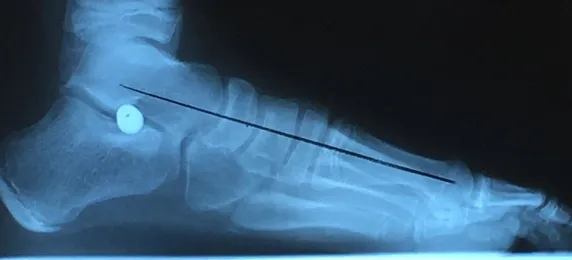

Pre and Postop Subtalar Implant and Percutaneous Achilles Lengthening Below. The first pics show wedging of the distal tibia physis causing ankle valgus due to constant pressure caused by the severity of the flatfoot (JT)